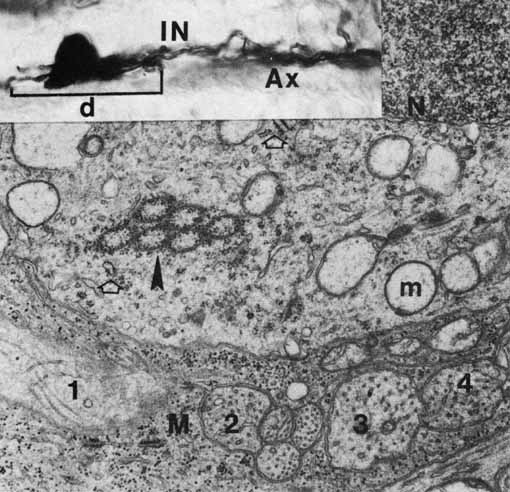

The photoreceptor outer segments have two important connections. One of these is to the inner segment, which is actually the cell body of the photoreceptor (see Fig. 21). The other connection is to the extracellular matrix that separates the photoreceptor outer segment from the pigment epithelial cell. Radioactive tracer experiments suggest that the sources of this extracellular matrix substance are the pigment epithelial and photoreceptor cells.99,100 The material, a glycoprotein consisting of chondroitin sulfate and sialic acid, is secreted into the space between the outer segments and the pigment epithelial cells by vesicles that originate in both cells. The function of this mucopolysaccharide-rich matrix is not well understood. It may provide a major route by which metabolites and nutrients pass between photoreceptor cells and their vascular supply. It may constitute the only intercellular bond between the outer segments of photoreceptors and the pigment epithelial cells, because there are no cellular connections such as tight junctions between these cells (see Fig. 23). Recent studies have identified interphotoreceptor retinol-binding protein as a major component of this matrix.100 This glycoprotein is believed to mediate the transport of a vitamin A derivative, retinol, between the photoreceptor and the pigment epithelium.

The connection of the outer to the inner segment of the photoreceptor is through a slender (0.2–0.3 μm in diameter) neck that is eccentric toward one side of the cell (see Fig. 21). The cilium, which is the embryonic basis for origin of the photoreceptors, is located in the neck and extends into the basal one third of the outer segment. It has nine pairs of microtubules. However, unlike motile cilia, the cilium has no microtubules centrally. The microtubules end in a modified centriole in the apex of the inner segment. The cilium functions as a conduit for metabolic materials going from the inner to the outer segments.

Inner Segments

The inner segment of the photoreceptor is the portion of the cell that metabolically services the outer segment. Whereas the outer segment shows high differentiation, containing only equipment necessary for the photoreceptor process, the inner segment possesses the cellular machinery essential for the metabolic and synthetic functions of the cell. There are two distinct morphologic regions in the inner segment, the ellipsoid and the myoid. The most prominent feature of the outer portion, or ellipsoid, of the inner segment is the abundance of large mitochondria at the apex (see Fig. 21). The ellipsoid appears to be more sensitive to anoxia than any other part of the photoreceptor cell.101 The staining characteristics of this area vary with the state of metabolic activity of the photoreceptor cell and may account for the subtle staining differences seen in the various types of photoreceptor cells. The mitochondria in the ellipsoid are compactly arranged. They are present in higher concentration in retinas with poor vasculature. In addition, the cones have a higher concentration and greater absolute number of mitochondria than the rods. There may be up to 600 mitochondria per cone.87 These mitochondria contain the normal enzymes for oxidative production of energy.102

The cilium or basal body arises from one of a pair of centrioles at right angles to one another in the distal portion of the ellipsoid. From the basal body originates the cross-striated fibril system of rootlets that course through the inner segment (see Fig. 21). The ciliary rootlets are composed of bundles of several hundred fibrils with a periodic alternation of light and dark zones 45 nm wide. They may extend as far as the nucleus of the cell. Their function remains speculative, although histochemical evidence suggests that they may play a role in energy or even in signal conduction. The energy-related enzyme, ATPase, has been found in the fibrils of these rootlets.103

The major protein synthetic activity and assembling of synthetic products in the inner segment take place at its proximal portion, or “myoid,” which houses the rough endoplasmic reticulum, ribosomes, and large Golgi complex associated with numerous vesicles. Because this region may be the source of the acid mucopolysaccharide in the extracellular space between the photoreceptor outer segments, disturbances of this synthetic or assembling facility could result in weakening of the normal retina-pigment epithelium adhesion. Such a defect could make this union more delicate and subject to separation in the presence of a retinal tear or exudative process originating from either the retina or the choroid.

Outer Nuclear Layer